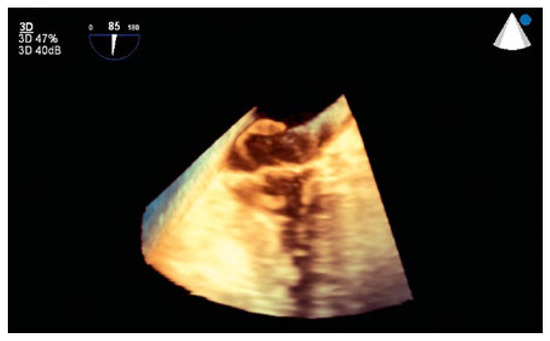

An 88-year-old man with a history of transient ischaemic attack, chronic kidney disease and primary hypertension presented with dyspnoea and was found to have large bilateral pulmonary emboli on a computedtomography angiogram of the chest [...]